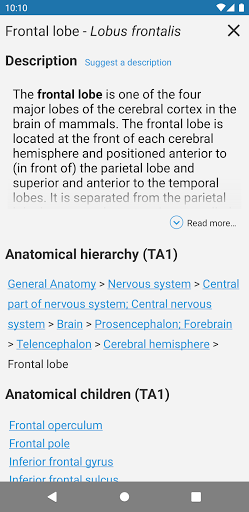

*Find your anatomical parts more easily thanks to the new, more intuitive and powerful search feature

*Improved visibility of anatomical parts definitions

*Browse between anatomical parts using description links